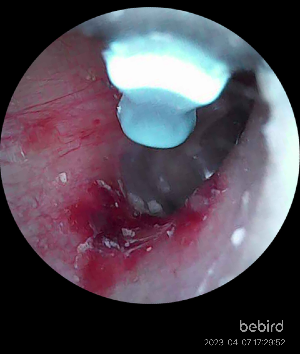

사실 이 후기를 쓰는 가장 큰 이유중 하나는 모자이크된 저 사진 때문이다.

(사진은 제일 마지막에 공개 예정. 약간의 징그러움 주의)

나에게 조심성이라고는 1도 없었고

카메라에 의지하여 귀 내시경을 움직이다 보니 귀 안쪽에서는 컨트롤이 어려웠다.

그렇게 나의 귀는 만신창이가 되었고

감을 잡아갈 때에는 귀가 너무 아파서 더이상 진행이 불가하였다...힝....

생각보다 귀 안쪽은 매우매우매우 연약한 부위였다.

귀 안쪽이 다 아물면 다시 도전해서 꼭 안쪽의 귀지를 제거하고야 말겠다....